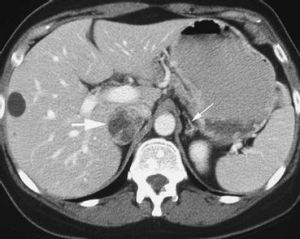

腎上腺囊腫多無症狀,常因體檢或其他原因檢查時發現,文獻中將之歸於腎上腺偶發瘤中,腎上腺囊腫較大時,可因壓迫周圍臟器出現腰腹部脹痛及胃腸道不適等非特異性症狀,少數患者可因囊腫破裂出血引起急腹症,手術探查時才被發現。可分為以下四型:1.內皮性囊腫

占45%,又分為淋巴瘤型和血管瘤型,囊壁內襯以光滑和平坦的內皮細胞為其特點。

2.假性囊腫

占39%,主要因腎上腺組織或腫瘤內出血所致,也可因腫瘤的囊性退行性

腎上腺囊腫3.上皮性囊腫

占9%,包括胚胎性囊腫,腎上腺囊腺瘤,真性或瀦留性囊腫3類,內壁襯以腺上皮細胞。

4.寄生蟲性囊腫

7%,以包蟲性囊腫為最多見,表現為壁厚,多鈣化,並可見頭節。